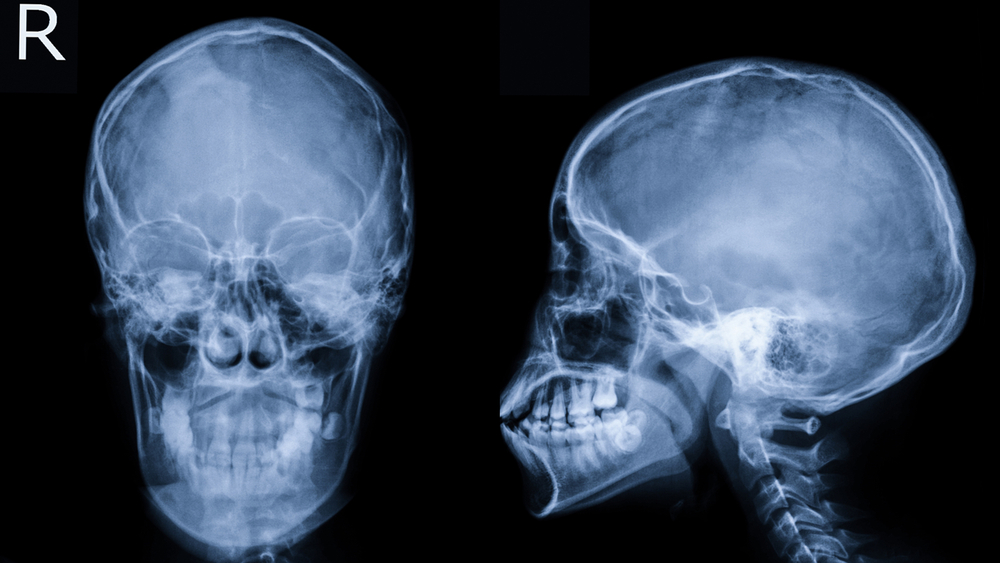

Finding Relief From TMJ: What You Need To Know About Today’s Technology

In the world of TMD (temporomandibular disorder), there are many ways to treat the problem, but it must always begin with a good diagnosis. First and foremost are an MRI and CBCT X-ray of the joints and surrounding areas. The MRI is a magnetic imaging device that looks directly at the discs in the jaw joints. This high-tech machine looks... read more »